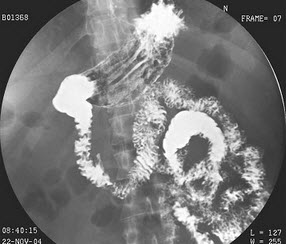

24、单项选择题

男,40岁,腹胀痛1月余。体检:脾肋下5cm,结合图像,最可能的诊断为()

A.正常食管

B.食管静脉曲张

C.食管胃底静脉曲张

D.贲门失弛缓

E.食管癌